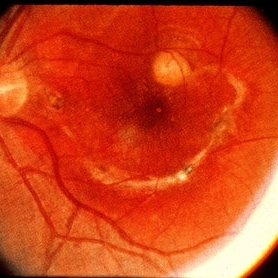

Childhood Acquired Ocular Toxoplasmosis

Childhood Acquired Ocular Toxoplasmosis

Sep 13 2023 by Deepak Bhojwani, MS

Fundus image of a 16 year old boy diaagnosed with Ocular Toxoplasmosis since the age of 10 years showing the classic toxo chorioretinitis scar on the posterior pole. Luckily the scar is loacted juxtatemporal to fovea on OCT and so the boy has good vision of 20/30.

Photographer: DR DEEPAK BHOJWANI

Imaging device: OPTCAL COHERENCE TOMOGRAPHY

Condition/keywords: posterior uveitis, toxo chorioretinitis